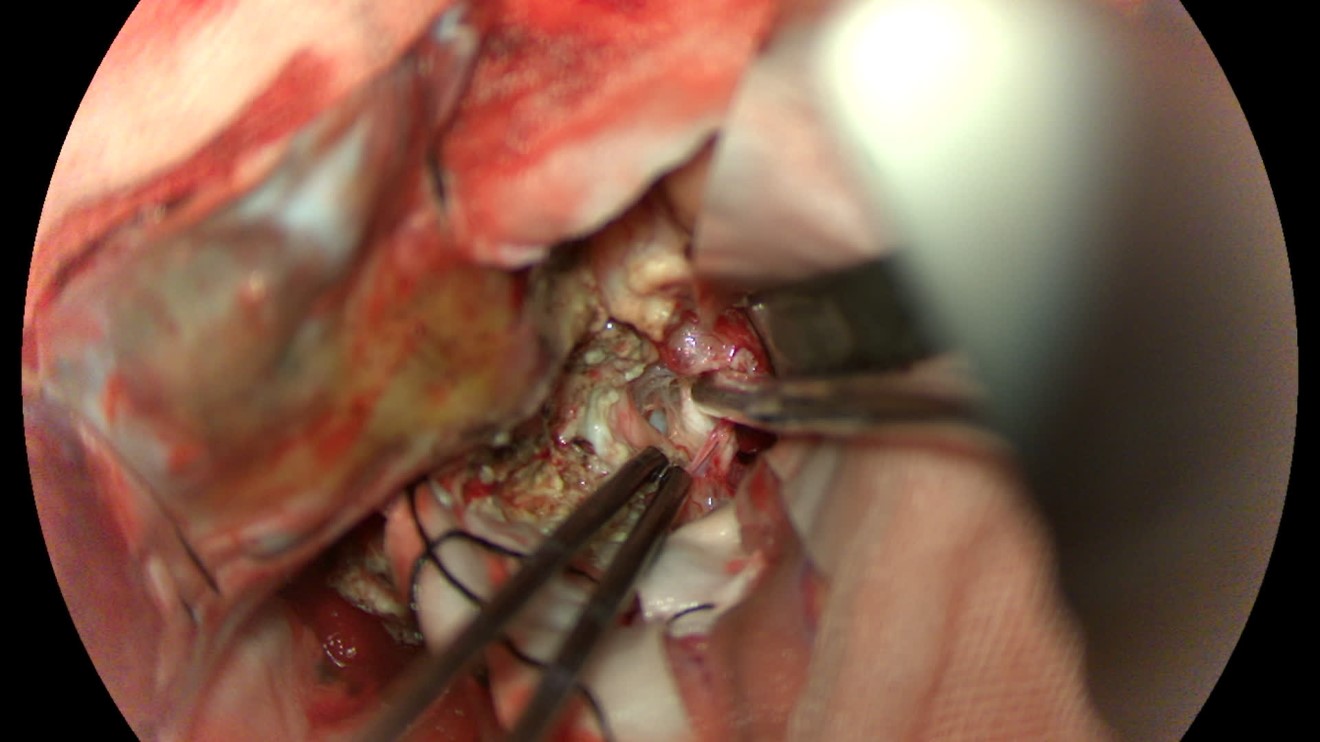

该患者入院后完善常规颅脑影像学检查,左侧颞叶病变,疾病性质不详,转移瘤、胶质瘤、炎症类疾病均不能排除,遂行PET-CT检查,提示左侧颞叶高代谢,淋巴瘤不能排除。组织MDT会诊建议可先行腰椎穿刺查脑脊液脱落细胞学、感染指标,若仍不能确诊,可进一步行开颅病灶切除,术中快速冰冻,根据冰冻结果决定手术手术策略。患者脑脊液脱落细胞学结果:较多淋巴细胞,少许单核细胞及个别中性粒细胞,未见异形细胞,脑脊液常规、生化、脑脊液培养未见细菌生长,诊断仍不能明确,且患者病情进展迅速,患者神志呈昏睡状态,颅脑MRI提示病变较前明显增大(影像学检查间隔两周),且水肿明显加重,遂行开颅病变切除术。术中见部分病变累及蝶骨嵴硬膜,病变质地硬韧,内有多个囊腔,囊内容物为黄色粘稠样脓性物质,留取囊液及实性部分送快速冰冻,在等待冰冻过程中,进一步探查见肿瘤侵犯左侧颞叶,该部位肿瘤质地相对软,无包膜,与周围脑组织无边界,血运不丰富,内有多个囊腔,且肿瘤侵犯侧裂池、颈动脉池,左侧视神经、颈内动脉、大脑中动脉均被病变包绕,且该处肿瘤质地偏硬韧。术中快速冰冻提示组织大片变性坏死,伴胶质增生及淋巴增生。结合病变质地及冰冻结果,考虑为非肿瘤性疾病,可能为炎性病变伴肉芽肿形成可能性大,且肿瘤质地硬韧,累及范围广泛,难以全切,遂行肿瘤大部分切除后结束手术。术后病理结果明确后予以伏立康唑、醋酸卡泊芬净抗真菌治疗。在治疗过程中患者先后出现脑出血、脑梗塞,最终因治疗周期长,花费高、效果不确定等因素,家属放弃治疗,于术后1月去世。